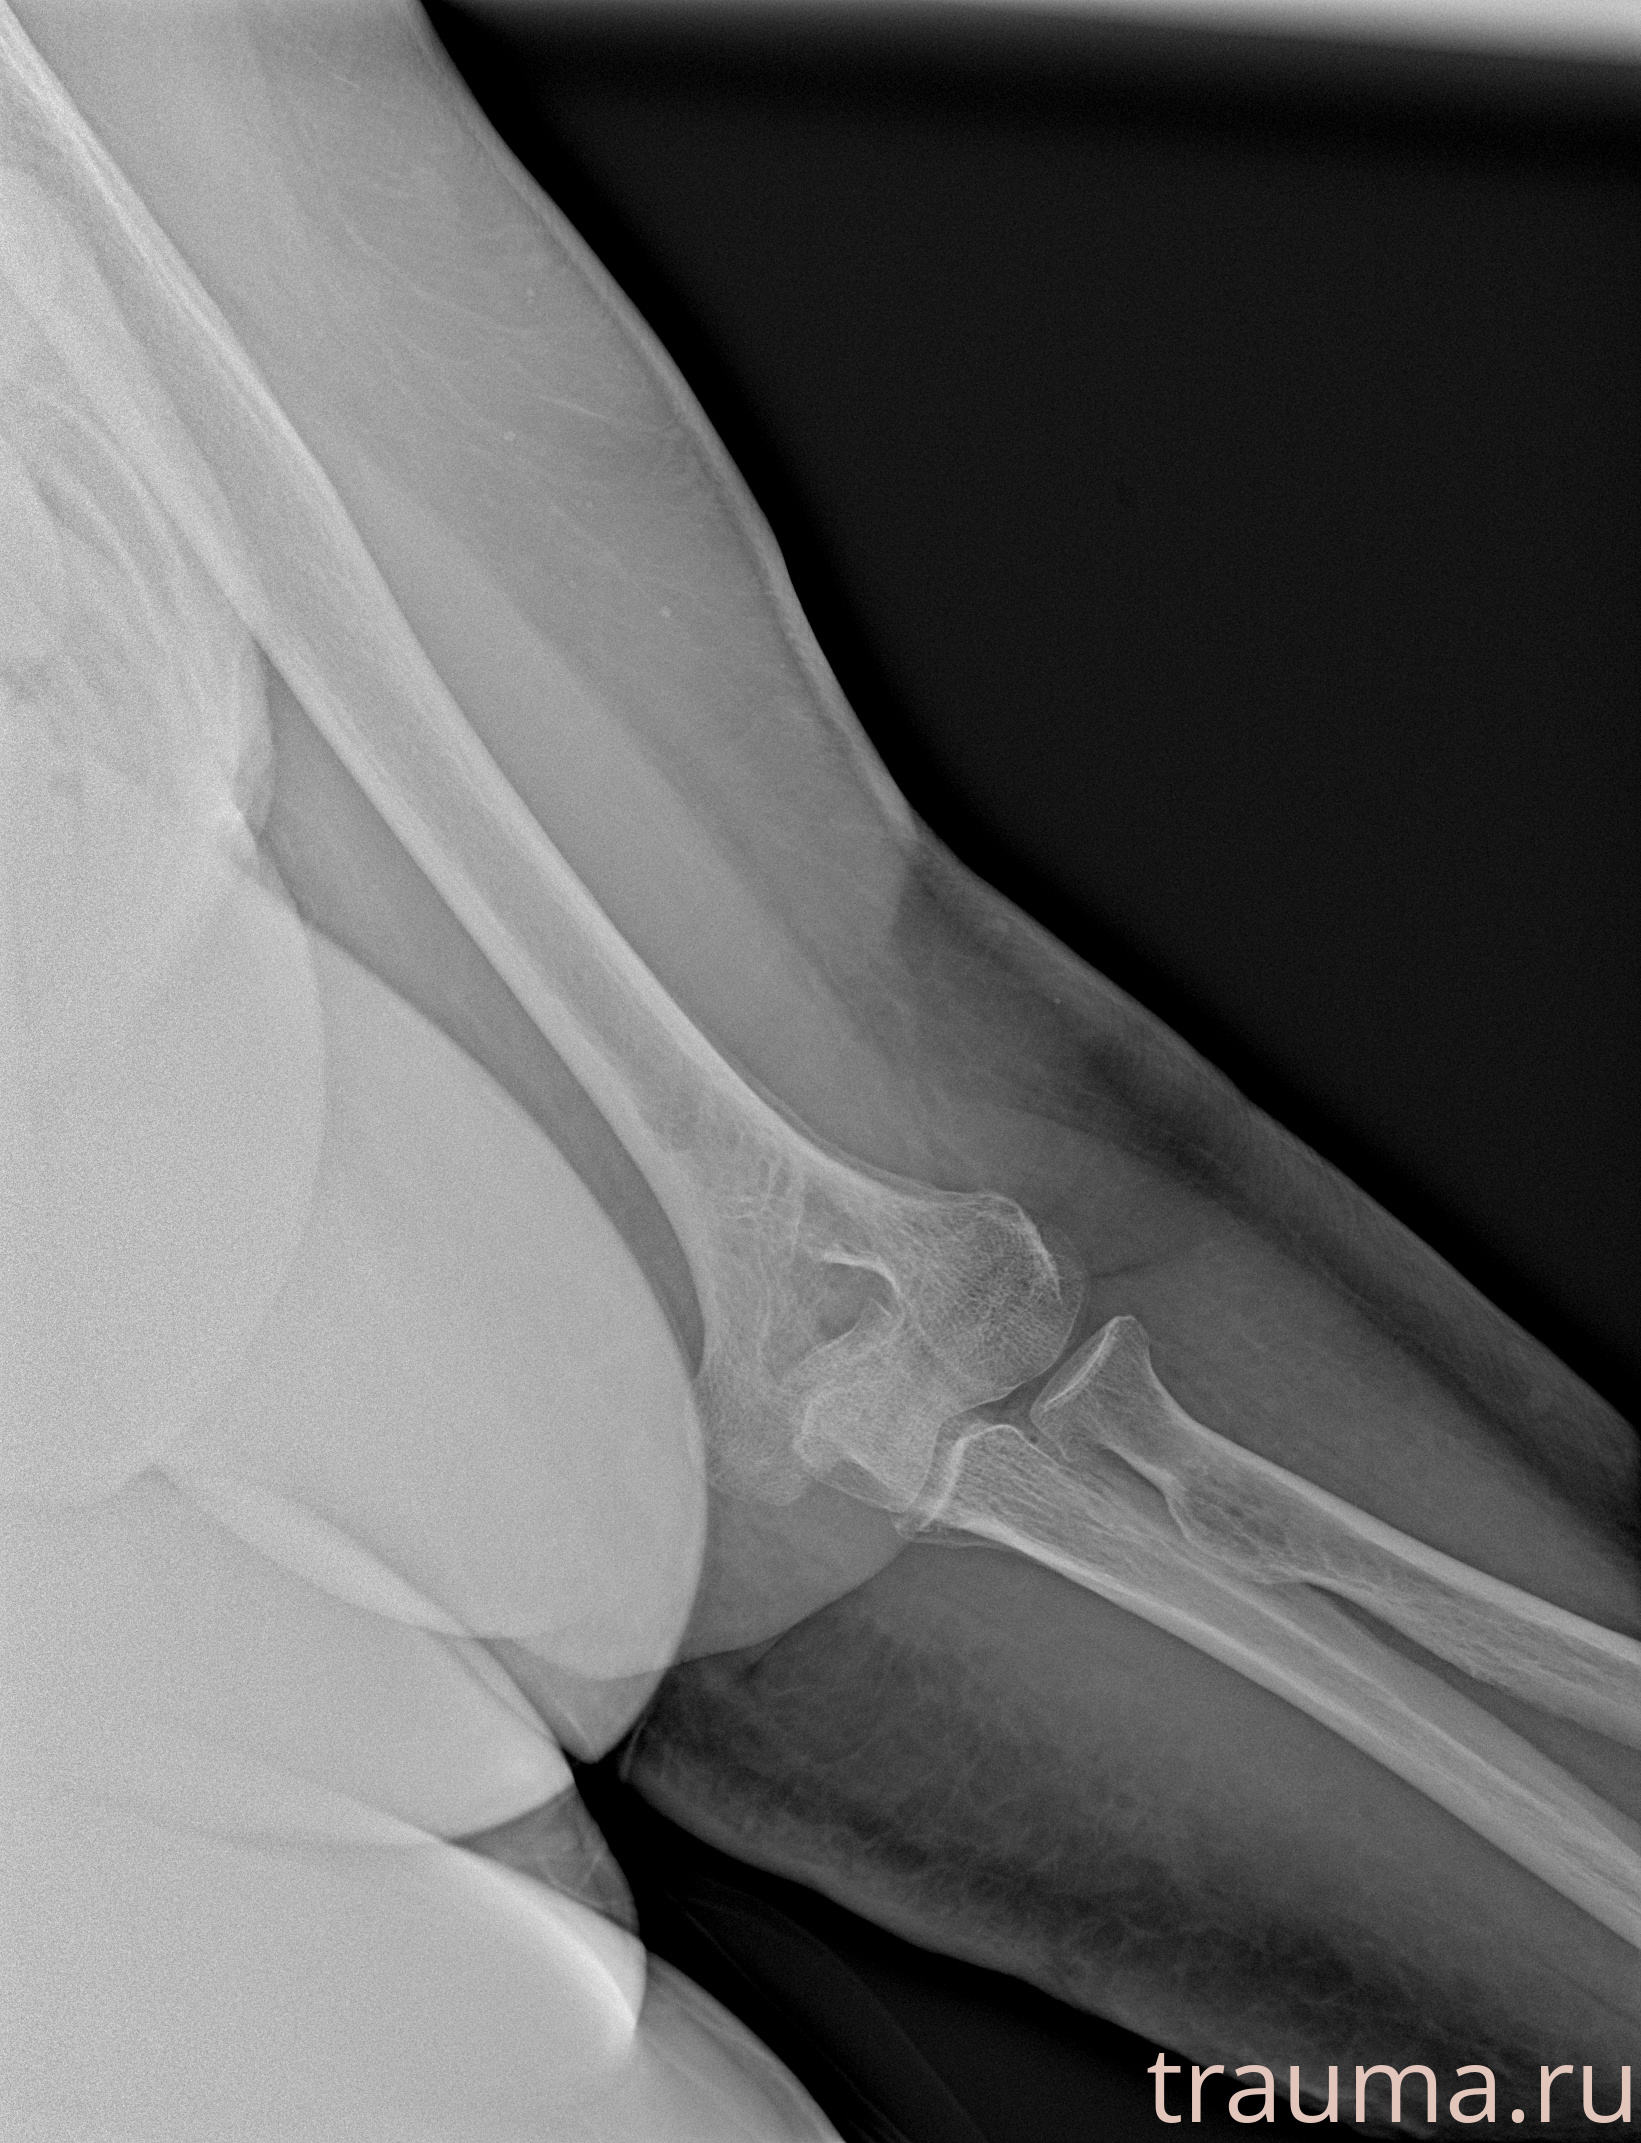

Рентген на дому: по вашему адресу приезжает врач-рентгенолог, травматолог-ортопед с мобильным рентгеновским аппаратом, проводит диагностику травмы или заболевания, делает необходимые рентгенограммы, дает рекомендации по дальнейшему лечению. Получить качественные снимки в домашних условиях возможно благодаря уникальной методике, разработанной МосРентген Центром для института  Склифосовского